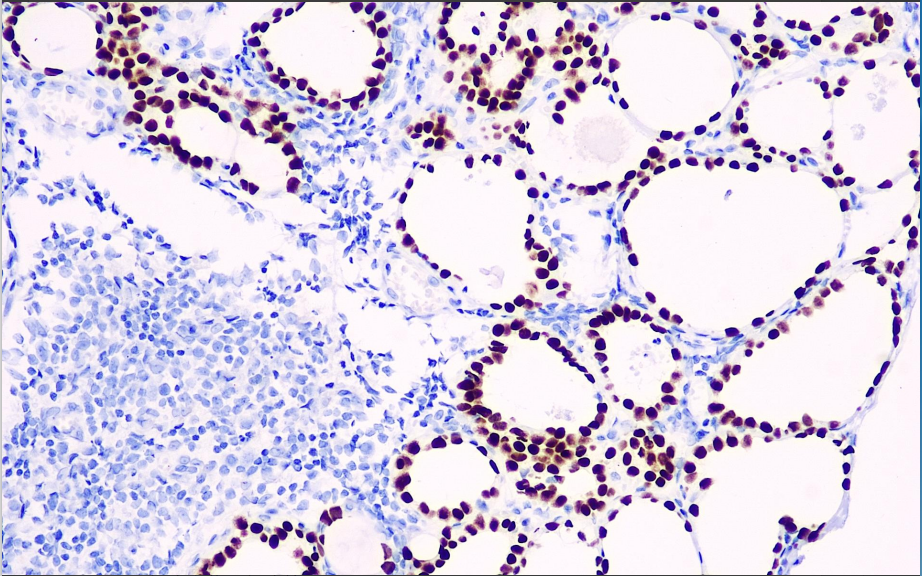

Positive control: Thyroid

Thyroid transcription factor-1 is a 4 kDa protein expressed mainly in epithelial cells of the thyroid and lung. The antibody is expressed positively in papillary thyroid carcinomas. In studies of lung tumors, immunohistochemical results were positive for TTF-1 in most small cell lung carcinomas, lung adenocarcinomas, most atypical lung neuroendocrine carcinomas, and a few large cell undifferentiated carcinomas of the lung, but negative in squamous carcinoma of the lung and most typical lung carcinoid tumors. This antibody is mainly used to classify lung and thyroid tumors and to distinguish lung adenocarcinomas from squamous carcinomas.